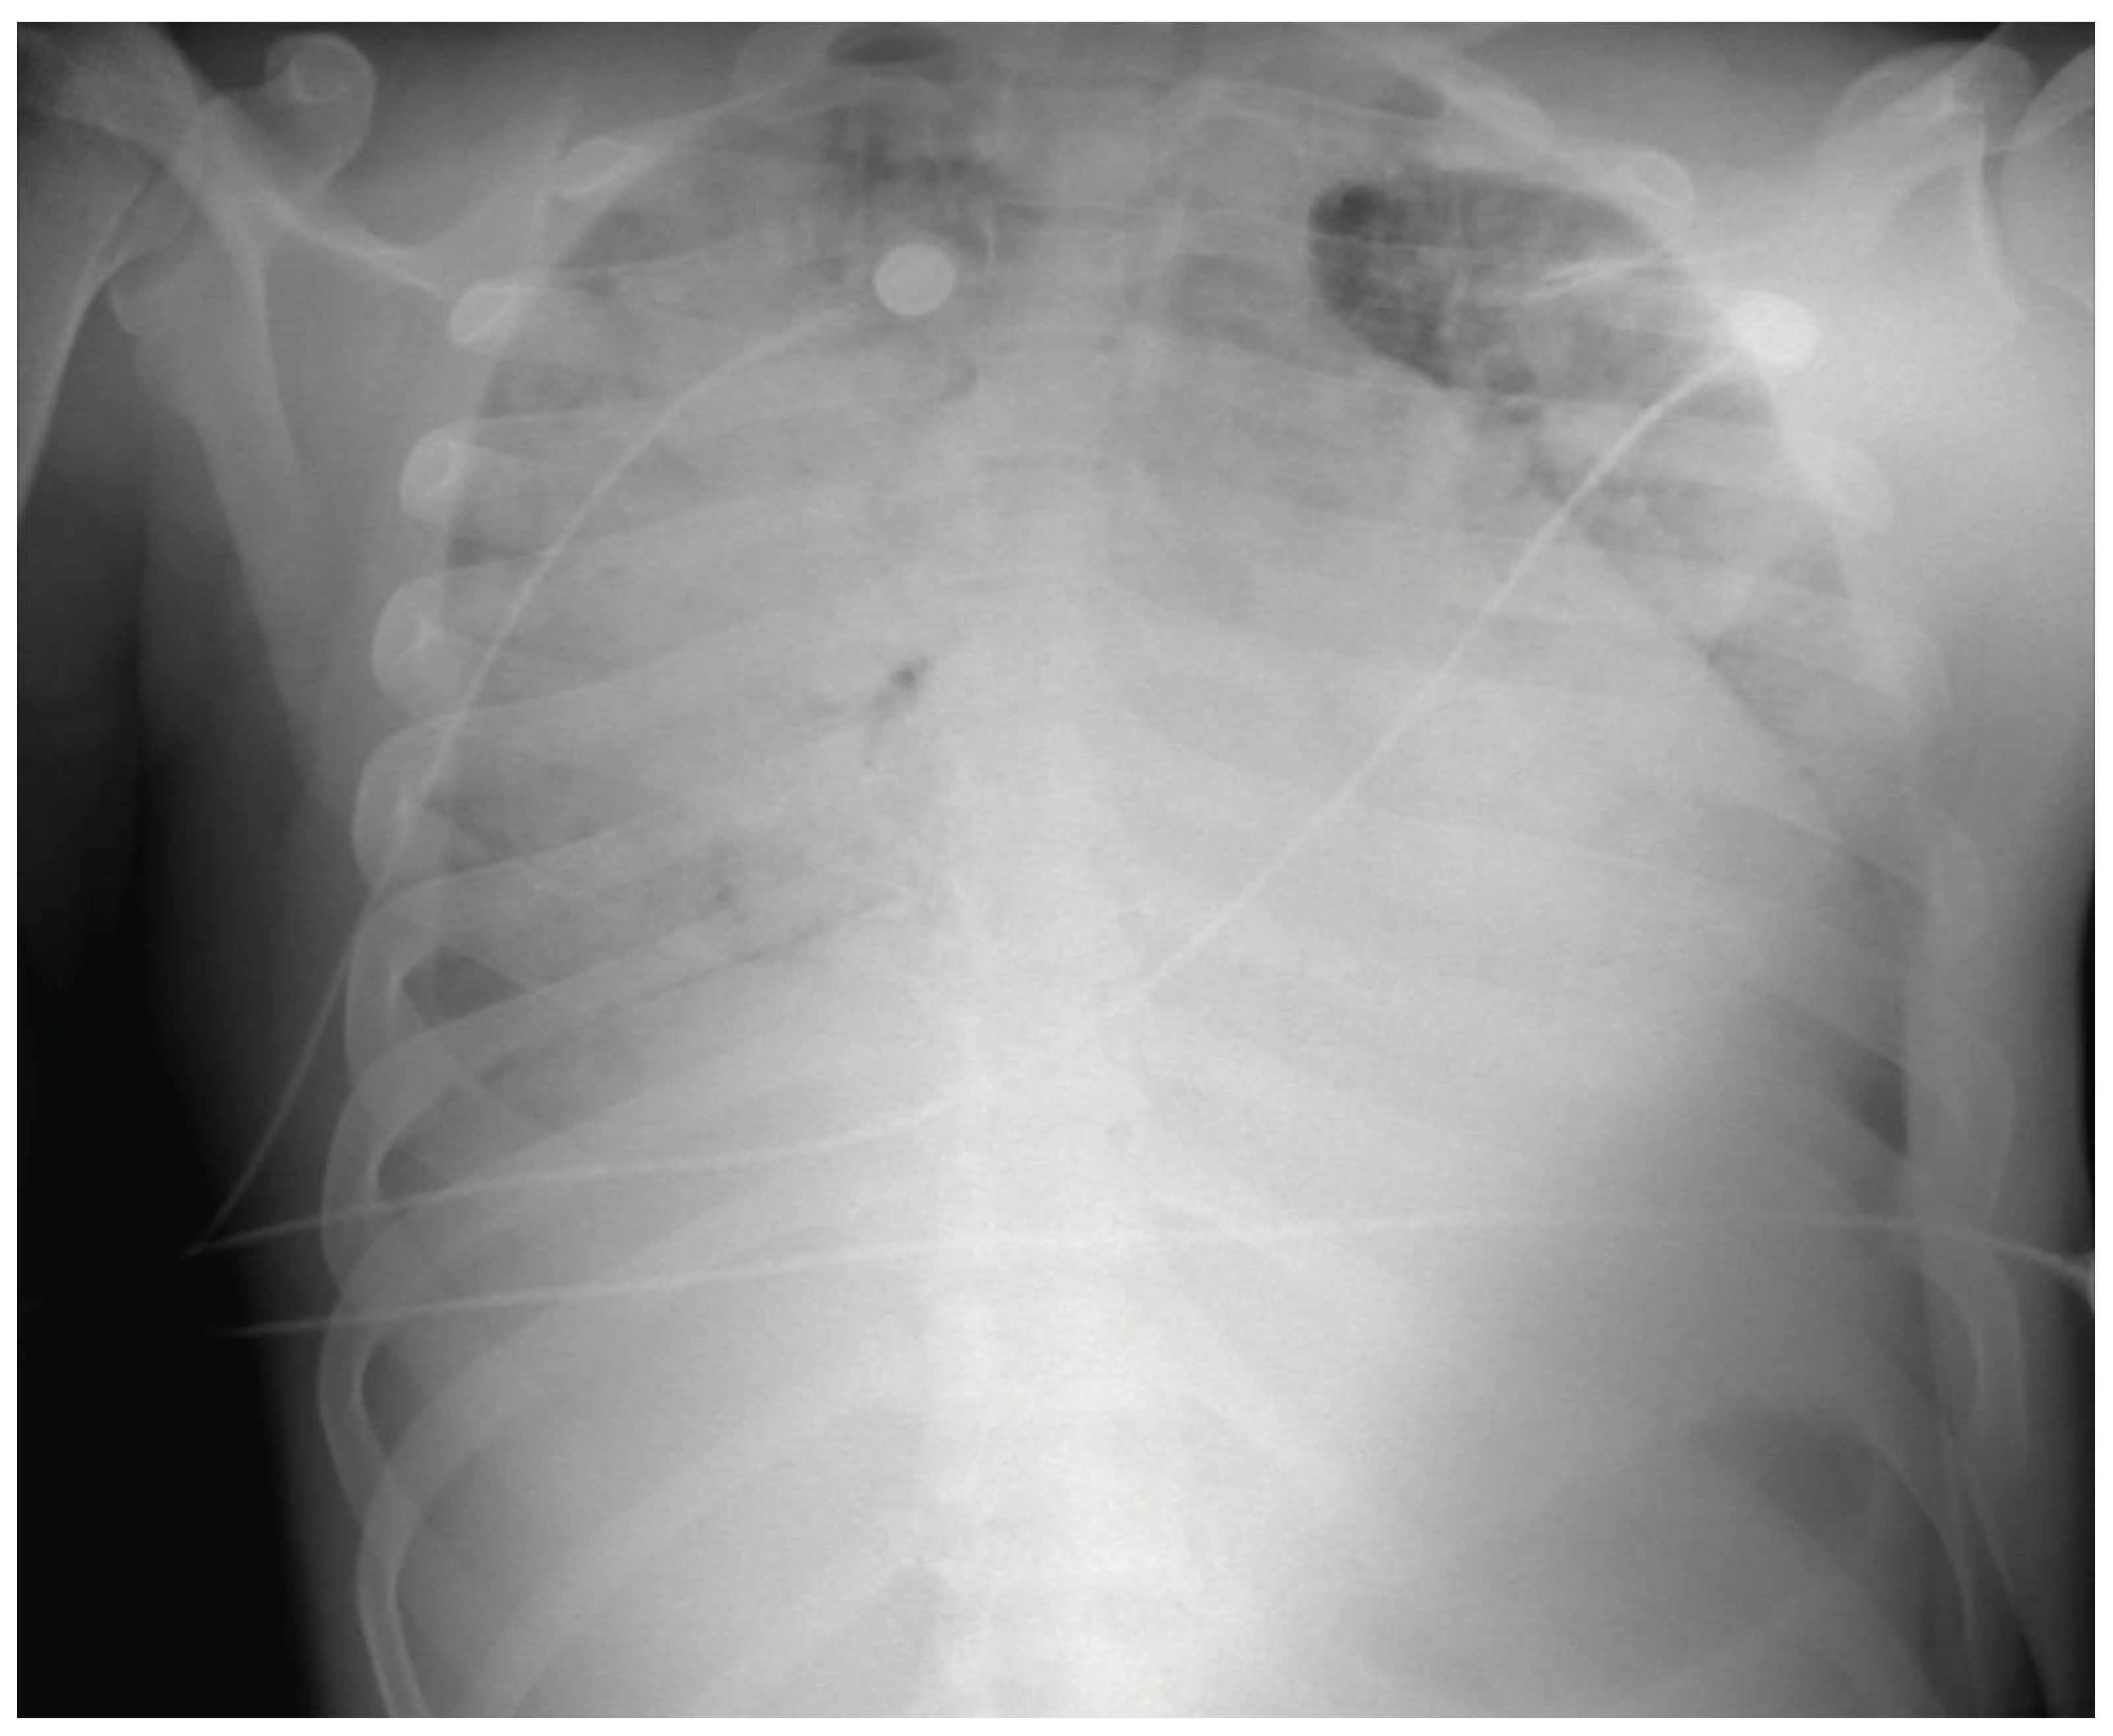

| Thoracic ultrasound (pericardium and pleura) | Bilateral pleural effusion, predominantly on the right side, not susceptible to drainage. | |||